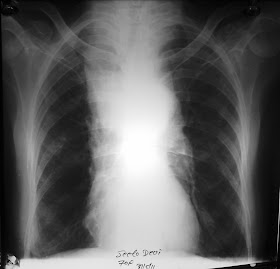

CT axial section of chest lung window in 50 year old male showing diffuse bilateral symmetrical patchy ground glass opacities with areas of air space opacities, interlobular septal thickening and peribronchovascular thickening. Features consistent with Pneumocystis carinii pneumonia.